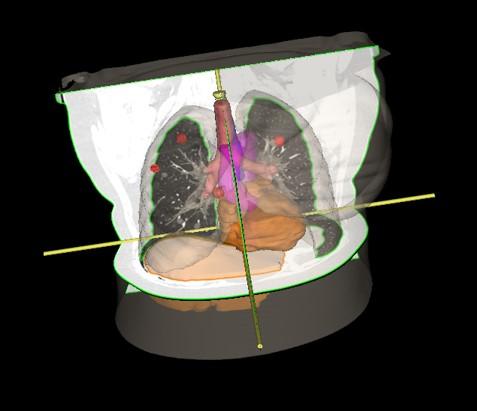

Pluća